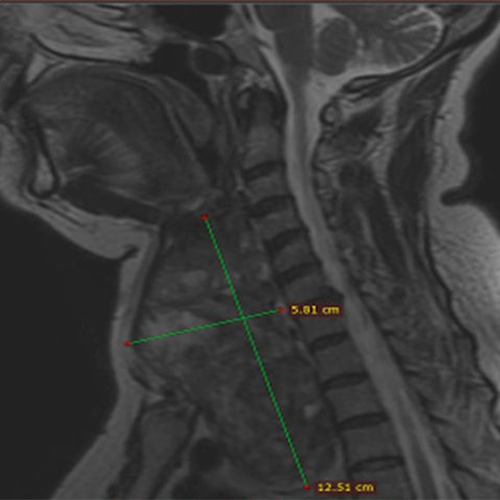

We performed thyroid embolization treatment in our 58-year-old patient with a 12cm giant nodule extending into the chest cavity causing severe dyspnea. A year later, the nodule shrank by 85%, the neck of the patient got slimmer, and shortness of breath disappeared completely. In addition, the mild hyperthyroidism previously present in the patient improved and the thyroid hormones returned to normal.